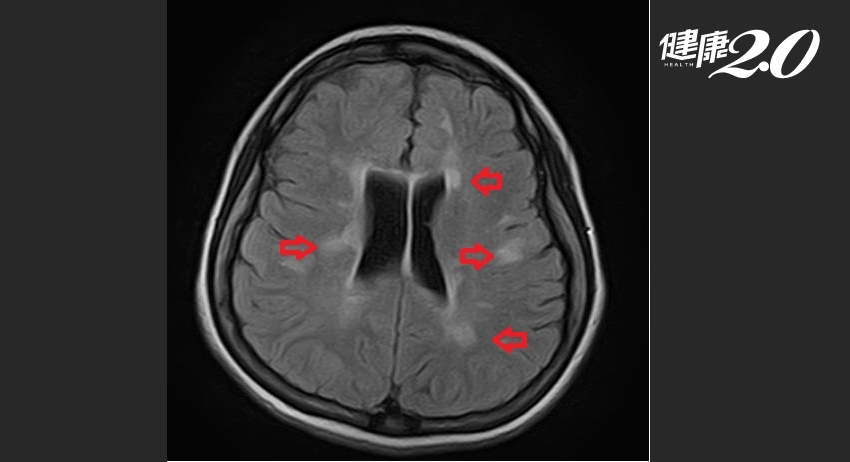

鄧浩文指出,在沒有三高或吸菸的年輕人身上,出現類似中風的局部神經症狀,通常非單純疾病,需要高度懷疑為腦部疾病,尤其可能是腦幹病變。少女經腦部核磁共振檢查,發現在右側的腦幹與小腦交界以及腦室周遭有多處疑似去髓鞘病灶的卵圓形斑塊,經過其他檢查,包括腦脊髓液檢查排除其他疾病後,確診是罹患多發性硬化症。

▲ 少女患者的右側腦幹與小腦交界、腦室周遭有多處卵圓形斑塊。